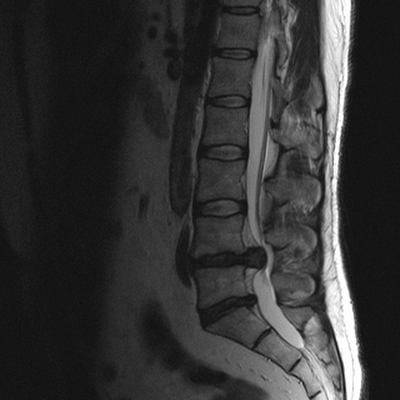

МРТ позвоночного столба: грыжа диска L4-L5 (сагиттальная плоскость, Т2 ВИ)

МРТ: межпозвонковая грыжа диска L4-5 (аксиальная проекция, Т2 ВИ)